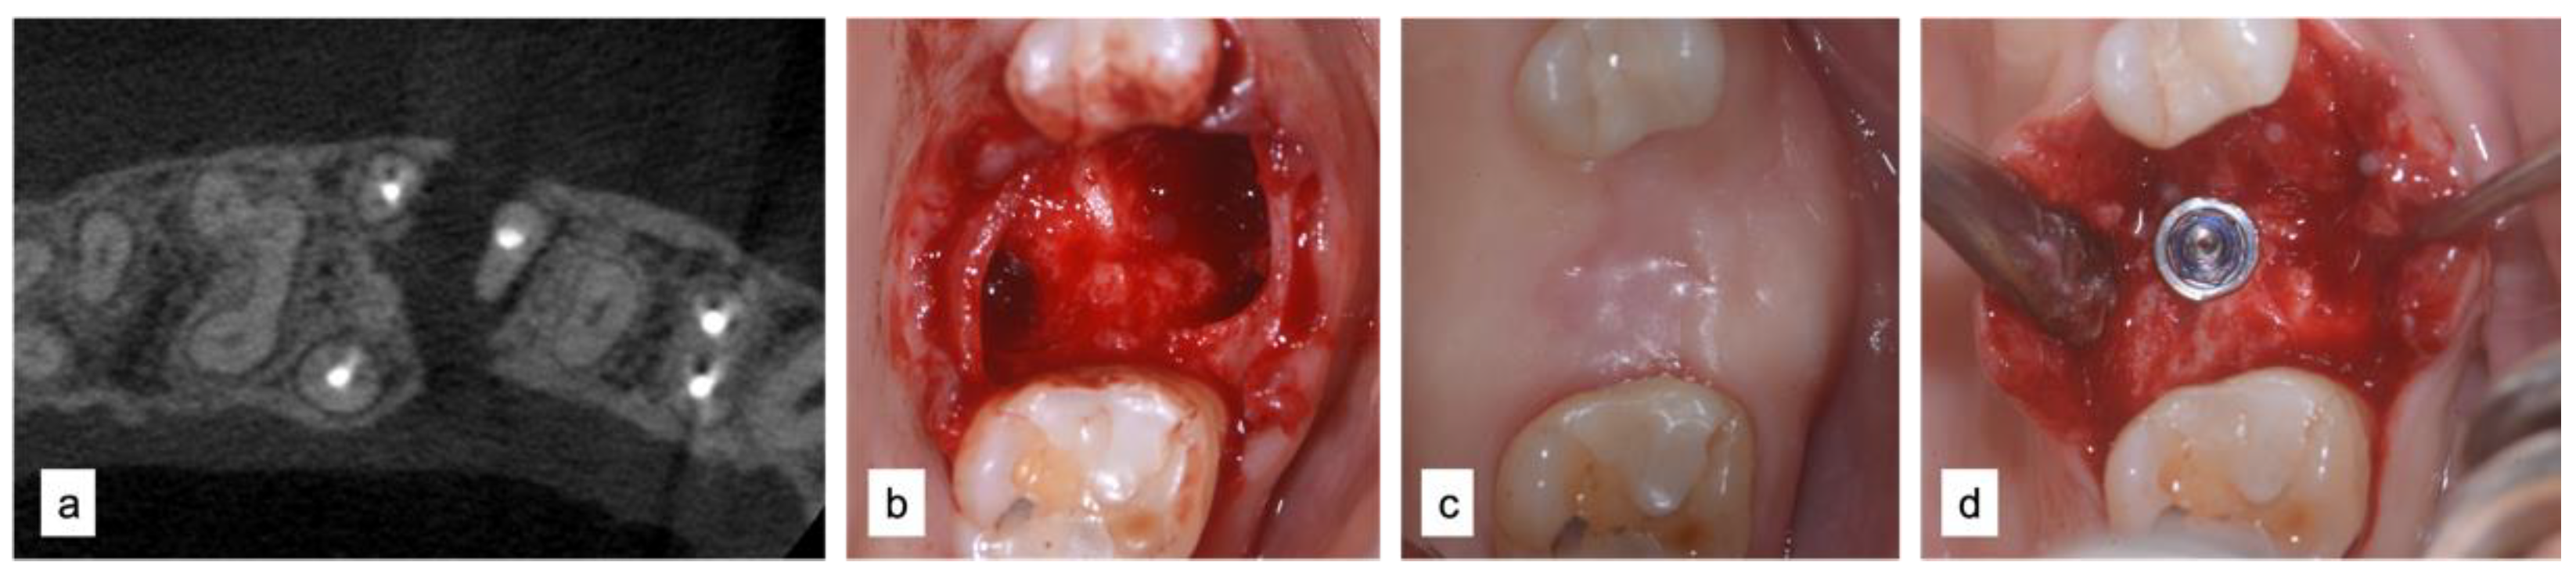

2.2.3. Case 6—MPI Technique Zone 16